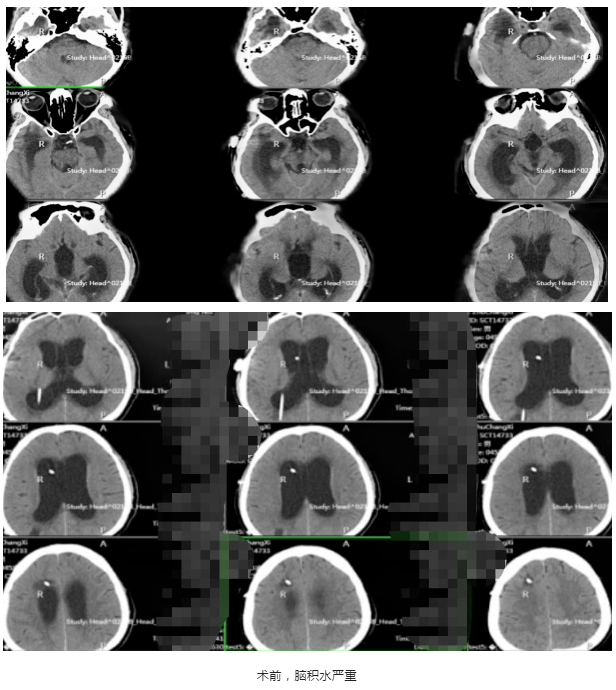

今年5月,周先生出现反复发热,一开始以为是感冒所致,就诊无效后,到医院检查发现,脑积水较之前扩张明显。同时,脑脊液培养痤疮丙酸杆菌,奥斯陆莫拉氏菌、肺炎链球菌等多种细菌,确诊颅内感染、分流管腹腔段感染。当地医院行脑室腹腔分流管储液囊持续外引流,后又行腹腔镜探查+脑室腹腔分流管松解术,术中见分流管窦道周围少许脓样分泌物,剪除末端分流管,并调整腹腔端位置,并进行抗感染治疗等系列治疗。治疗近一个多月,复查CT显示脑积水较前进一步进展,患者情况却越来越糟糕,也陷入昏迷,呼唤言语不清,无睁眼。

入院后,张金锋博士安排对周先生进行系统检查,发现颅内感染及腹腔感染依旧严重,脑积水进行性进展。经过科室讨论,林志雄教授、张金锋博士认为,要彻底治疗首先要缓解脑积水进展,并进行抗感染治疗,让脑脊液充分净化,保证原有的杂质没有,原有的顽固细菌全部被杀死并且不再复发,脑脊液清亮,一切达标之后再做脑积水分流术,解决脑积水难题。

7月1日,林志雄教授、张金锋博士为患者全麻下行“右侧枕角Ommaya囊去除术+右侧额角脑室腹腔分流管腹腔端外置术”,手术顺利。术后予以抗感染、营养神经、雾化化痰、补液、营养支持等系列治疗,并定期复查脑脊液常规、生化、培养,复查脑积水也评估抗感染效果。经过一段时间治疗,周先生的脑脊液充分净化,复查脑脊液结果正常,颅内感染控制良好。他的身体状态也越来越好,也从昏迷状态清醒,肢体各项功能也得到了恢复,进食、记忆力也都恢复得不错。